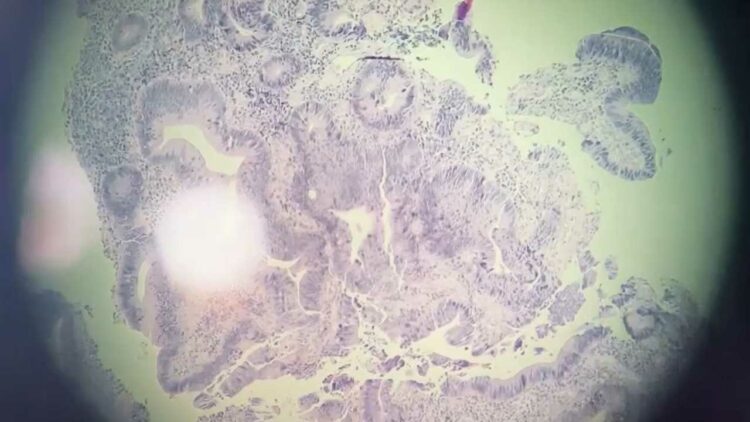

В онкодиспансере Челнов показали, как выглядят раковые клетки

В онкодиспансере Набережных Челнов рассказали о работе врачей-морфологов гистологической лаборатории, пишут «Челнинские известия».

Они принимают особое участие в диагностике раковых заболеваний. Под микроскопом врачи-морфологи изучают раковые клетки и исследуют новые технологии.

Так, в Онкодиспансере Набережных Челнов внедрили технологии, которые позволяют получать пациентам иммунотерапию. Ее применяют при немелкоклеточном раке легкого, с раком эндометрия, шейки матки, молочной железы и других видов заболевания.

«Механизм иммунотерапии рака заключается в том, что препарат позволяет иммунитету «увидеть» опухоль и уничтожить её», — заявили в медучреждении.